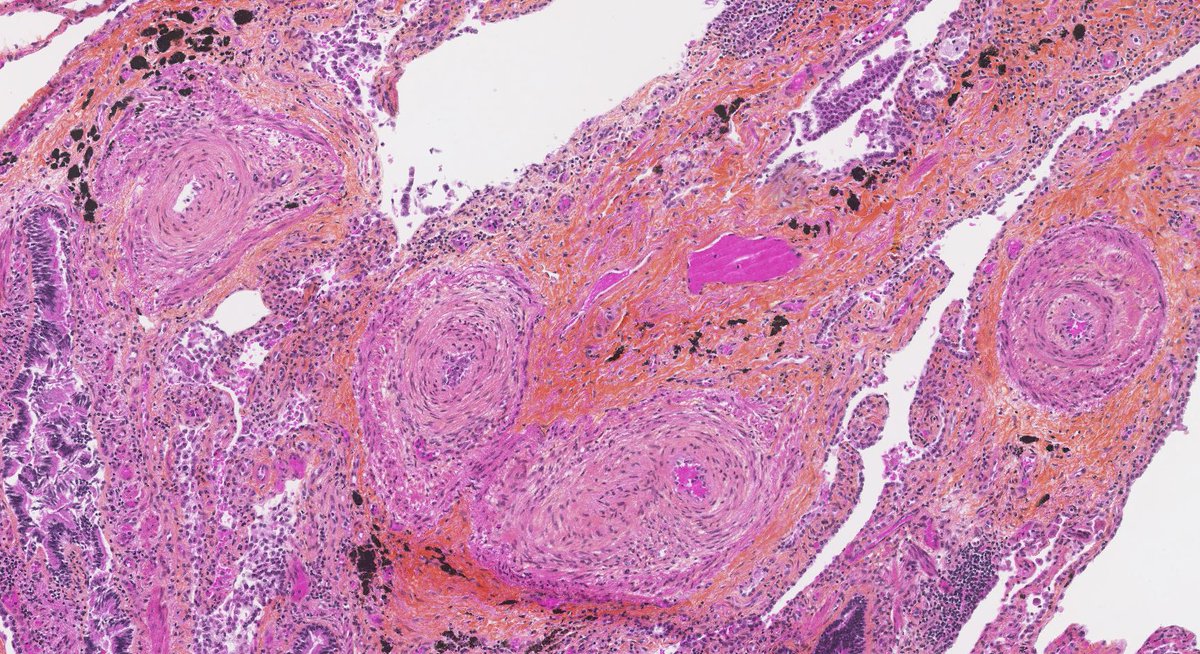

Explants from woman in her mid 40s. Clinical history on req: pulmonary hypertension. IHC is CD1a. Unifying diagnosis?

Thanks to all who engaged! Although uncommon, chronic LCH can lead to severe secondary pulmonary HTN which is what we see here. A spectrum of arterial lesions, including plexiform, dilatation, and medial hypertrophy. Wishing the patient a new lease on life with new lungs!